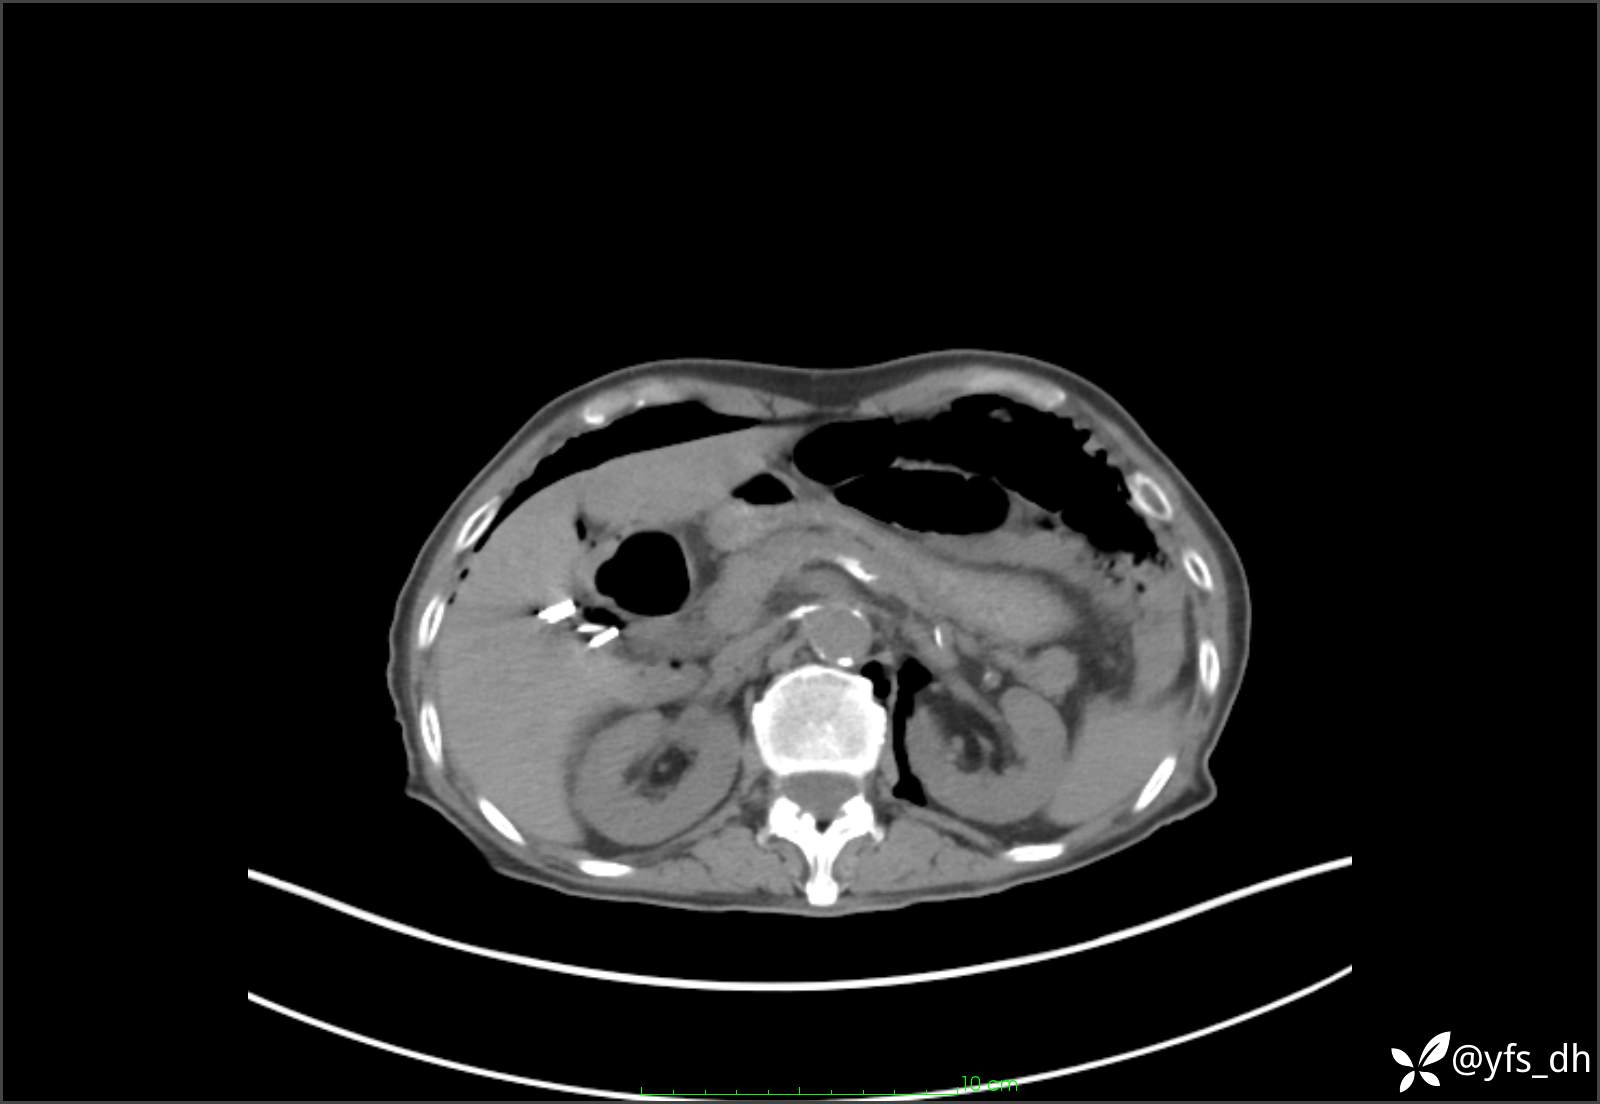

1.简要病史:患者4天前突发上腹部疼痛不适,但可以忍受。3小时前饭后突然加重,不能忍受后就诊。

2.简要手术记录:术中见腹盆腔大量肠液及粪便,乙状结肠中下段见一约3cm的破口。